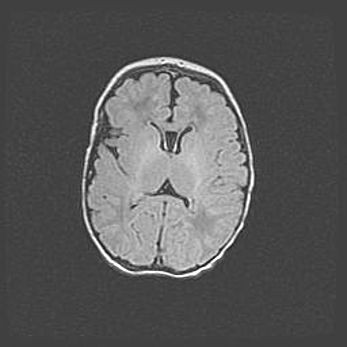

Сообщающаяся гидроцефалия. Кистозная энцефаломаляция головного мозга.

Возраст: 3 месяца 4 дня

Вес: 3100 г

Пол: женский

Окружность головы: 34 см

Срок гестации: 31 неделя

Кистозная энцефаломаляция головного мозга - одна из форм поражения головного мозга в детском возрасте. Характеризуется возникновением множественных и распространённых кист в коре, белом веществе и подкорковых образованиях головного мозга у плодов, новорождённых и детей раннего возраста. Развитие кистозной энцефаломаляции связано с внутриутробной асфиксией и гипотонией, родовой травмой, тромбозом синусов, пороками развития сосудов, инфекциями, сепсисом и другими причинами. Наиболее значимые инфекционные агенты: вирусы простого герпеса, цитомегалии, краснухи, токсоплазмы, энтеробактерии, золотистый стафилококк и другие.